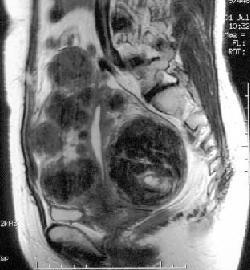

はじめまして。キューオーエル(株)北沢真澄と申します。19歳の頃から卵巣嚢腫や多発性の子宮筋腫をかかえ、月経過多・月経痛・メンタルの激しい浮き沈みに悩んできました。度重なる開腹手術・ホルモン剤による治療を行うも、とっても小さくしてもまたまたたくさんできてきて、お腹の中いっぱいに大きくなる子宮筋腫。良性の腫瘍で、30代以降の女性に多く、40代の女性では4人に1人にみつかるといわれるくらいポピュラーな病気です。(日本産婦人科医会HPより)

(2001年北沢腹部MRI画像)